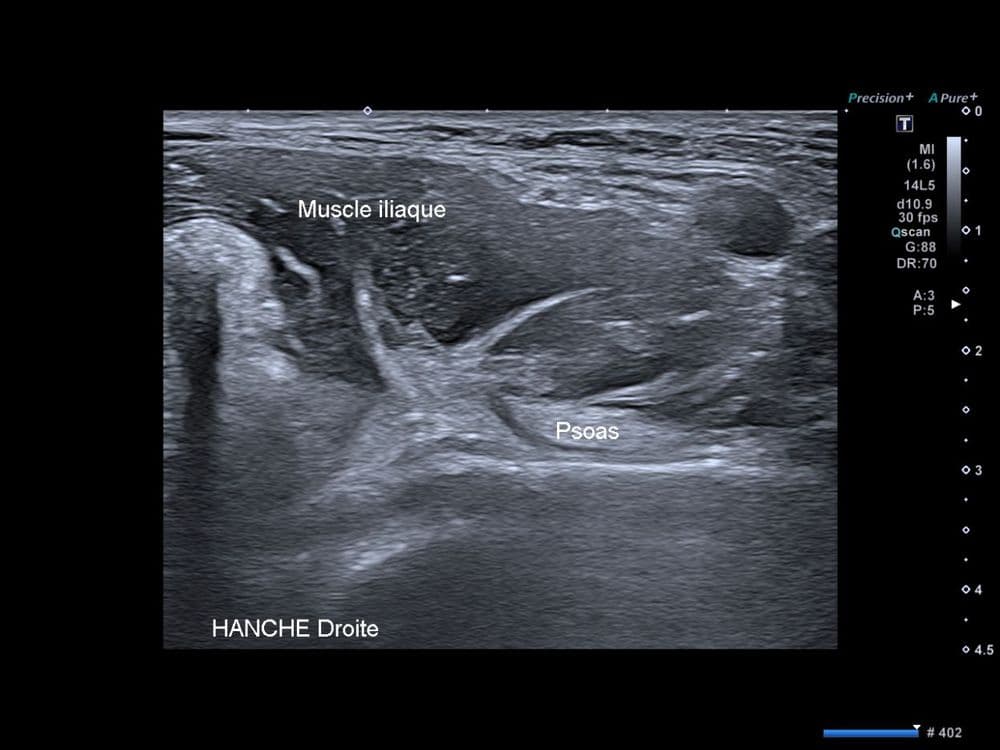

Echographie dynamique dans l'exploration d'un ressaut antérieur de hanche.

US